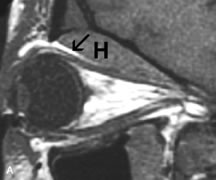

Although soft tissue relationships are usually better demonstrated on MRI, the evaluation of craniofacial bony trauma is preferable with CT. For example, prolapse of orbital fat through a fracture site and hemorrhage of adjacent tissues are demonstrated in an MR image, but the actual fractured bone is not imaged. Three-dimensional MRI of the orbit in subacute trauma has been described,58 although its precise role is not currently established. MRI has been suggested to be superior to CT in detecting intraorbital wooden foreign bodies.59,60 In a series of penetrating orbital injuries with organic foreign bodies, however, MRI was able to identify the foreign body in only four of seven cases.61 With an in vitro model for wood foreign body, McGuckin and colleagues concluded that CT was the imaging modality of choice.62 A careful history and, in selected cases, plain films to rule out a metallic foreign body are crucial before MRI is considered in patients with periocular trauma.

MRI is particularly helpful in the detection and characterization of subperiosteal hematomas of the orbit (Fig. 19). They are most commonly seen in the subperiosteal space of the superior orbit as well-defined masses following a traumatic injury. The signal intensity varies depending on the acute, subacute, or chronic nature of the hematoma, based on the stage of blood degradation. Fresh hemorrhages are hypointense on T1-weighted images and hyperintense on T2 images. Hematomas that are 1 to 7 days old are hypointense on both T1- and T2-weighted images. T1-weighted images of hematomas more than a week old are hyperintense due to the oxidation of deoxyhemoglobin to methemoglobin, whereas the T2 images remain hypointense.63

Fig. 19. A. T1- and (B) T2-weighted MR scans demonstrate a large acute subperiosteal hematoma (H) that lies between the cortical bone of the orbital roof and the inferiorly displaced periorthira (double arrow). The extracopal fat (arrow) and levator muscle are displaced inferiorly.